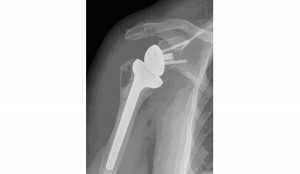

D’Arcy Johnson Day lawyer Steven Johnson recently obtained a $237,500 settlement for a 76 year old client who sustained a fractured shoulder as a result of a fall outside a commercial business property. The property owner had neglected to maintain the surrounding area resulting in a dangerous condition that led to the accident and injury. Before filing the lawsuit, the insurance company representing the property owner refused to offer any money to our client, and even worse, refused to even help pay for any medical treatment which required a prosthetic be inserted into our client’s shoulder.